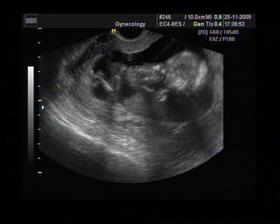

8/10 jsme se byli podívat u paní doktorky, zda testy nelhaly - a ono n e. Puclík měřil 0,37cm a co je důležité - srdíčko už funguje. Táta s Pepínem byli v ordinaci s námi, a když se na monitoru objevilo mimi, tak ho Pepíno pozdravil - udělal mu "ahoj" 🙂 oba nás to s Honzou dojalo. Další kontrola 22/10.